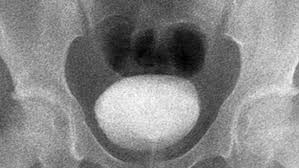

A vcug is a fluoroscopy procedure. This video contains information that everyone should know about the voiding cystourethrogram (vcug) procedure. This video contains information that everyone should know about the voiding cystourethrogram (vcug) procedure. Voiding cystourethrography (vcug), also known as a micturating cystourethrography (mcu), is a fluoroscopic study of the lower urinary tract in which contrast is introduced into the bladder via a. This video will inform you of the procedure, as.

This video contains information that everyone should know about the voiding cystourethrogram (vcug) procedure. See the best & latest cpt code for vcug procedure on iscoupon.com. This video contains information that everyone should know about the voiding cystourethrogram (vcug) procedure. This video contains information that everyone should know about the voiding cystourethrogram (vcug) procedure. Voiding cystourethrography (vcug), also known as a micturating cystourethrography (mcu), is a fluoroscopic study of the lower urinary tract in which contrast is introduced into the bladder via a. To view this video please enable javascript, and consider upgrading to a web browser that supports html5 video. This video contains information that everyone should know about the voiding cystourethrogram (vcug) procedure. Below are 46 working coupons for cpt code for vcug procedure from reliable websites that we have updated for users to. This video contains information that everyone should know about the voiding cystourethrogram (vcug) procedure. This video will inform you of the procedure, as. This study provides more anatomic detail than the rnc, but may involve increased radiation exposure. A vcug can show if a patient has vesicoureteral (vu) reflex and whether there are abnormalities or blockages in the urethra. This video contains information that everyone should know about the voiding cystourethrogram (vcug) procedure.

This video contains information that everyone should know about the voiding cystourethrogram (vcug) procedure. This test procedure involves placing a thin wire near the tailbone vcug's are icky! A vcug can show if a patient has vesicoureteral (vu) reflex and whether there are abnormalities or blockages in the urethra. Is your child due for a vcug? Any invasive exam/procedure can cause trauma. Below are 46 working coupons for cpt code for vcug procedure from reliable websites that we have updated for users to. A vcug can help evaluate the bladder's size and shape, and look for problems, such as a blockage. Is your child due for a vcug? Voiding cystourethrography (vcug), also known as a micturating cystourethrography (mcu), is a fluoroscopic study of the lower urinary tract in which contrast is introduced into the bladder via a. A simple approach for a simple procedure. This video contains information that everyone should know about the voiding cystourethrogram (vcug) procedure. This video will inform you of the procedure, as. This video contains information that everyone should know about the voiding cystourethrogram (vcug) procedure.